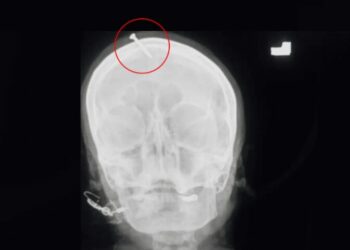

Uma mulher gr\u00e1vida escapou da morte ap\u00f3s martelar um prego na pr\u00f3pria cabe\u00e7a, depois que um curandeiro deu a dica para que ela tivesse um beb\u00ea do sexo masculino. O caso ocorreu em Pexauar, capital da prov\u00edncia Khyber Pakhtunkhwa, no Paquist\u00e3o.<\/p>\n\n\n\n

De acordo com a pol\u00edcia local, a v\u00edtima teria dado entrada no hospital da cidade com o prego cravado na cabe\u00e7a e apesar de objeto ter penetrado o cr\u00e2nio da mulher, n\u00e3o chegou a atingir o c\u00e9rebro e a gr\u00e1vida n\u00e3o corre risco de morte.<\/p>\n\n\n\n

Segundo informa\u00e7\u00e3o da ag\u00eancia DW, ap\u00f3s as autoridades policiais tomarem conhecimento do caso uma equipe foi designada para investigar o caso e chegar at\u00e9 o curandeiro uma vez que ele incentivou o ato que poderia ter tirado a vida da mulher.<\/p>\n\n\n\n

A pol\u00edcia tamb\u00e9m ir\u00e1 investigar o motivo de o m\u00e9dico assistente que atendeu a gr\u00e1vida n\u00e3o ter comunidade o fato imediatamente \u00e0s autoridades, que s\u00f3 tiveram conhecimento ap\u00f3s a imagem do raio x da v\u00edtima ser compartilhada nas redes sociais e viralizar.<\/p>\n","post_title":"Gr\u00e1vida martela prego na pr\u00f3pria cabe\u00e7a ap\u00f3s curandeiro \u2018dar dica\u2019 para beb\u00ea nascer menino","post_excerpt":"A mulher deu entrada em um hospital da cidade e apesar de o prego ter atravessado o cr\u00e2nio, n\u00e3o atingiu o c\u00e9rebro.","post_status":"publish","comment_status":"open","ping_status":"open","post_password":"","post_name":"gravida-martela-prego-na-propria-cabeca-apos-curandeiro-dar-dica-para-bebe-nascer-menino","to_ping":"","pinged":"","post_modified":"2022-02-12 10:52:38","post_modified_gmt":"2022-02-12 14:52:38","post_content_filtered":"","post_parent":0,"guid":"https:\/\/estadodoamazonas.com\/?p=25072","menu_order":0,"post_type":"post","post_mime_type":"","comment_count":"0","filter":"raw"}],"next":false,"prev":false,"total_page":1},"paged":1,"column_class":"jeg_col_2o3","class":"jnews_block_5"};